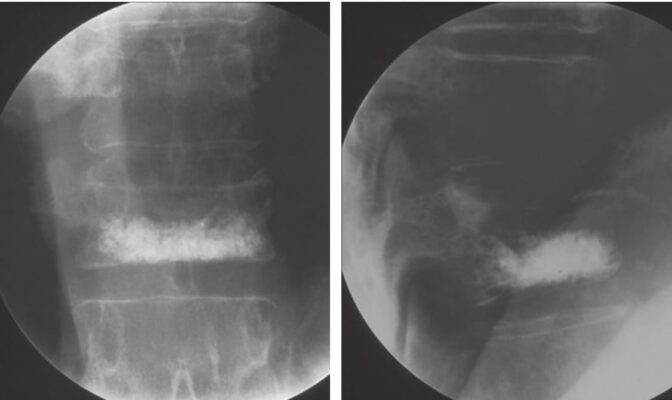

Các thủ thuật xâm lấn nói chung là không cần thiết. Một số bệnh nhân gãy xương cấp hoặc bán cấp không đáp ứng với điều trị bảo tồn có thể được điều trị bằng tạo hình đốt sống qua da (vertebroplasty hay là kyphoplasty) bằng cách tiêm “xi măng” xương (polymethyl methacrylate) để giảm đau, làm vững đốt sống và cải thiện chức năng.

Các kỹ thuật này có thể làm giảm biến dạng ở các thân đốt sống được bơm, nhưng không làm giảm và thậm chí có thể làm tăng nguy cơ gãy xương ở các đốt sống lân cận. Các nguy cơ khác bao gồm gãy xương sườn, rò xi măng, phù phổi cấp hoặc nhồi máu cơ tim.